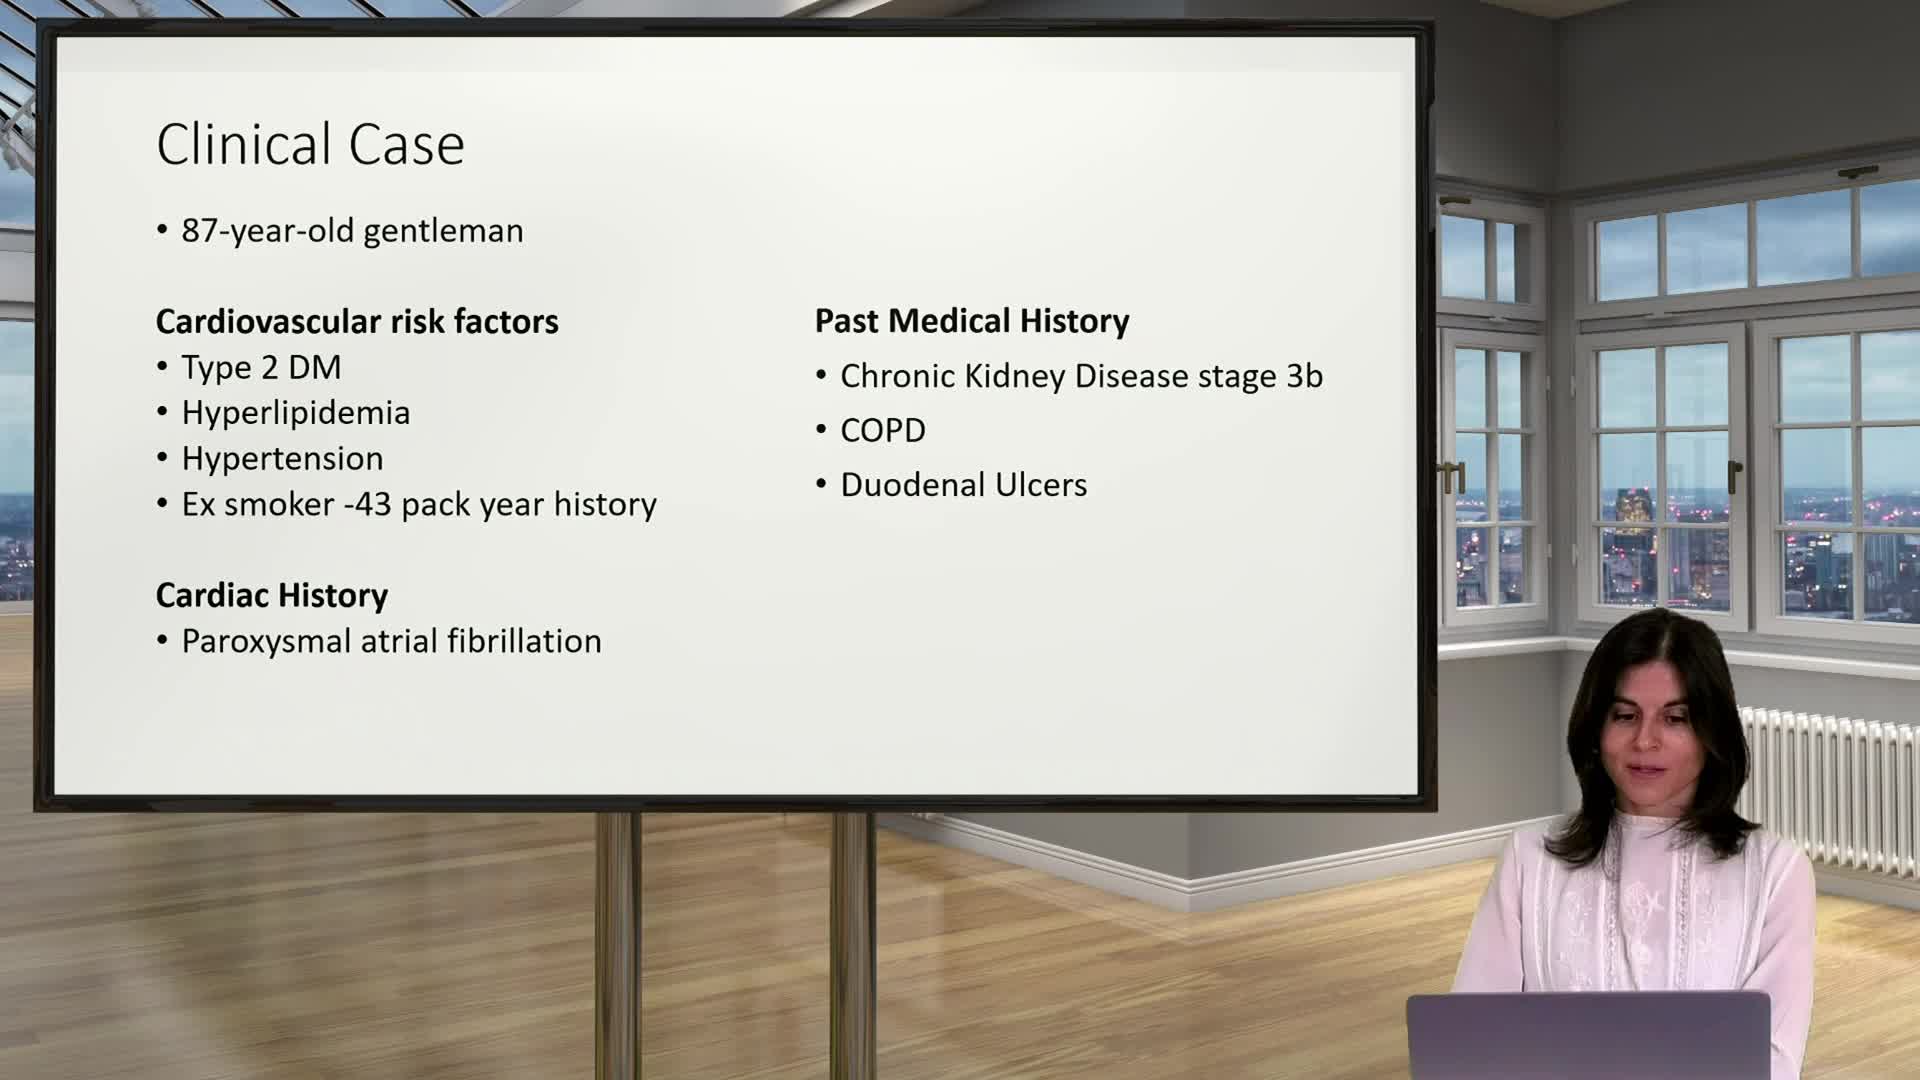

Ultralow Contrast PCI in complex and high risk patients - April 2024 Day One

Ultralow Contrast PCI in complex and high risk patients - April 2024 Day Two

Ultralow Contrast PCI in complex and high risk patients - November 2023 Day One

Ultralow Contrast PCI in complex and high risk patients - November 2023 Day Two

Ultralow Contrast PCI in complex and high risk patients - June 2023 Day One

Ultralow Contrast PCI in complex and high risk patients - June 2023 Day Two